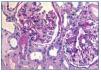

La biopsia renal mostró glomeruloesclerosis segmentaria y difusa con formación de nódulos eosinófilos PAS positivos (figura 1). Las arteriolas presentaban hialinosis franca PAS positiva y el intersticio mostraba fibrosis marcada con infiltrados difusos inflamatorios formados por linfocitos maduros y numerosos eosinófilos que producían imágenes de tubulitis (figura 2). La inmunofluorescencia resultó débilmente positiva para IgM mesangial, sin otros hallazgos. El rojo Congo fue negativo.

Figura 1. Biopsia renal. Imagen de microscopía óptica con tinción de hematoxilina-eosina. La imagen muestra lesiones de Kimmelstiel Wilson (glomeruloesclerosis nodular) e hialinosis arteriolar. Imagen cedida por Dr. Javier Gómez (Servicio de Anatomía Patológica. Hospital Universitario Marqués de Valdecilla, Santander).

Por tanto, el diagnóstico histológico fue de nefropatía diabética (glomeruloesclerosis nodular y difusa con hialinosis arteriolar) y nefropatía túbulo-intersticial con eosinofilia sugestiva de toxicidad farmacológica.